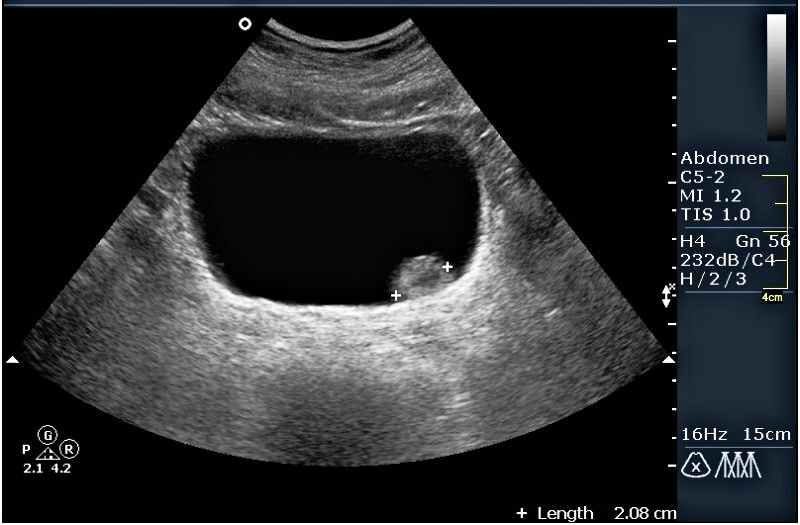

Прочитайте условие задачи. Рассмотрите эхограмму мочевого пузыря. Опишите эхограмму и дайте ультразвуковое заключение.

Мужчина, 73 года. Обратился к урологу с жалобами на учащенное мочеиспускание. При проведение УЗИ мочевого пузыря были замечено следующее очаговое изменение в мочевом пузыре: